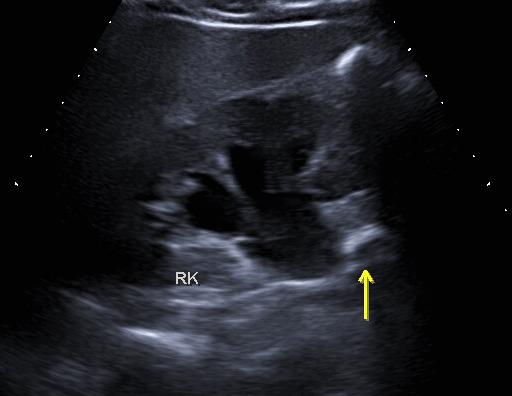

看,上面那个结石就已经走到输尿管了。

此时因为较大,堵住了输尿管,导致肾脏内的尿液排不出去,所以就会腰疼。